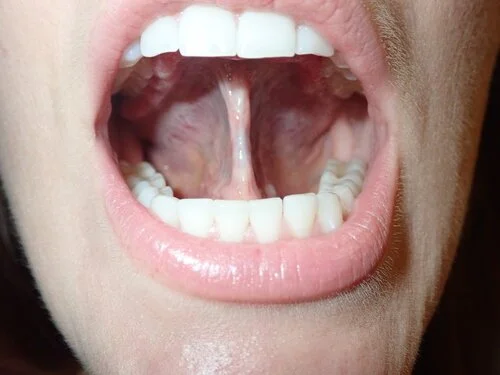

6 months post Lingual Frenectomy in habituation phase of Orofacial Myofunctional Therapy.

We continued her Orofacial Myofunctional Therapy and obtained optimal results. Patients stated her shoulder tension has been greatly reduced and her sleep quality has drastically improved.

case study image of case 6 months post release

case study image of list 6 months post release